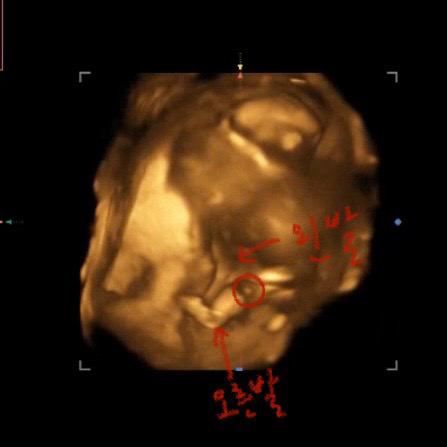

동그라미 친 부분 🌶️일까요...?!

13주차 때라 정확하진 않지만.. 입체초음파 때 발견한건데 🌶️아니죠? 지금은 16주차고, 17주차 때 병원갈 예정이라 성별 확인할 수 있을텐데 괜히 기다리기가 힘들고 막 그러네용 ㅎㅎ

많이 궁금하실거같아요ㅎㅎ 전 첫째때 딱 저래서 딸이라고 무조건적으로 믿고 의사쌤한테도 딸이냐고 물어봤는데 아직은 모른다고 하셨거든요 ㅎㅎ 근대 딸이었어여 ㅋㅋ 둘째는 12주때인데도 미사일이 너무 잘 보여서 제가 묻지도 않았는데 둘째는 아빠닮았다고 힌트주시더라구여 ㅎㅎ 성별 정말 궁금하실거같은데 조금만 기다려주면 곧 알게되실거에요☺️